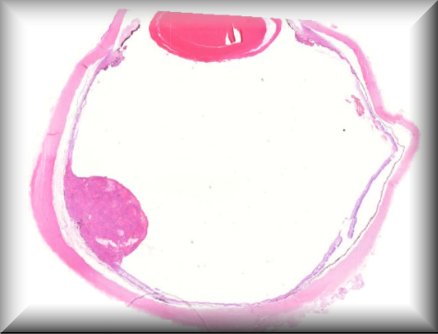

Tero Kivela: Anterior chamber extension of retinoblastoma |